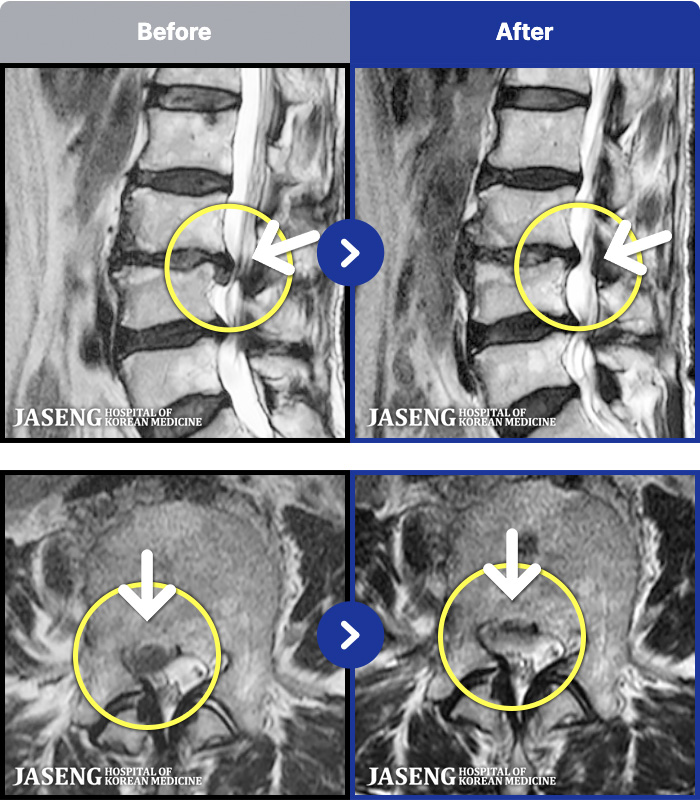

- MRI ġ

MRI ġ

1,237 MRI ũ ʸ Ȯϼ.